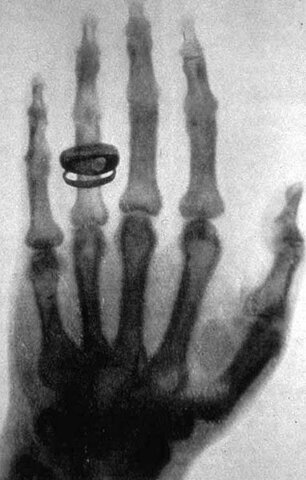

• Placas de fijación de fracturas óseas y rayos X

Placas de fijación de fracturas óseas y rayos X

W. A. Lane desarrolla un sistema de tornillos de carbón para placas de fijación de fractura de huesos y un par de años más tarde, William Roentgen descubre los Rayos X, los cuales se transforman en una herramienta insustituible de diagnóstico en la ortopedia y traumatología.